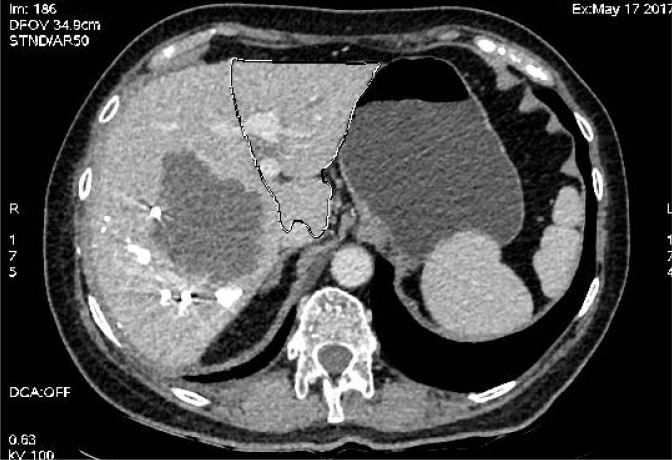

In patients with synchronic liver colorectal metastasis, resection of the primary tumor and liver metastases is the only potentially curative strategy. In such cases, there is no consensus on whether resection of the primary tumor and metastases should be performed simultaneously or whether a staged approach should be performed (resection of the primary tumor and after, hepatectomy, or hepatectomy first). Patients with no bowel occlusion and with extensive liver disease are advised neoadjuvant oncological therapy. Similarly, various strategies such as portal vein embolization, liver deprivation, two-staged hepatectomy, and associating liver partition and portal vein ligation are available for patients who do not have a sufficient future liver remnant (generally 30-40% of the total). Therefore, a multidisciplinary approach is required for the treatment of these patients.